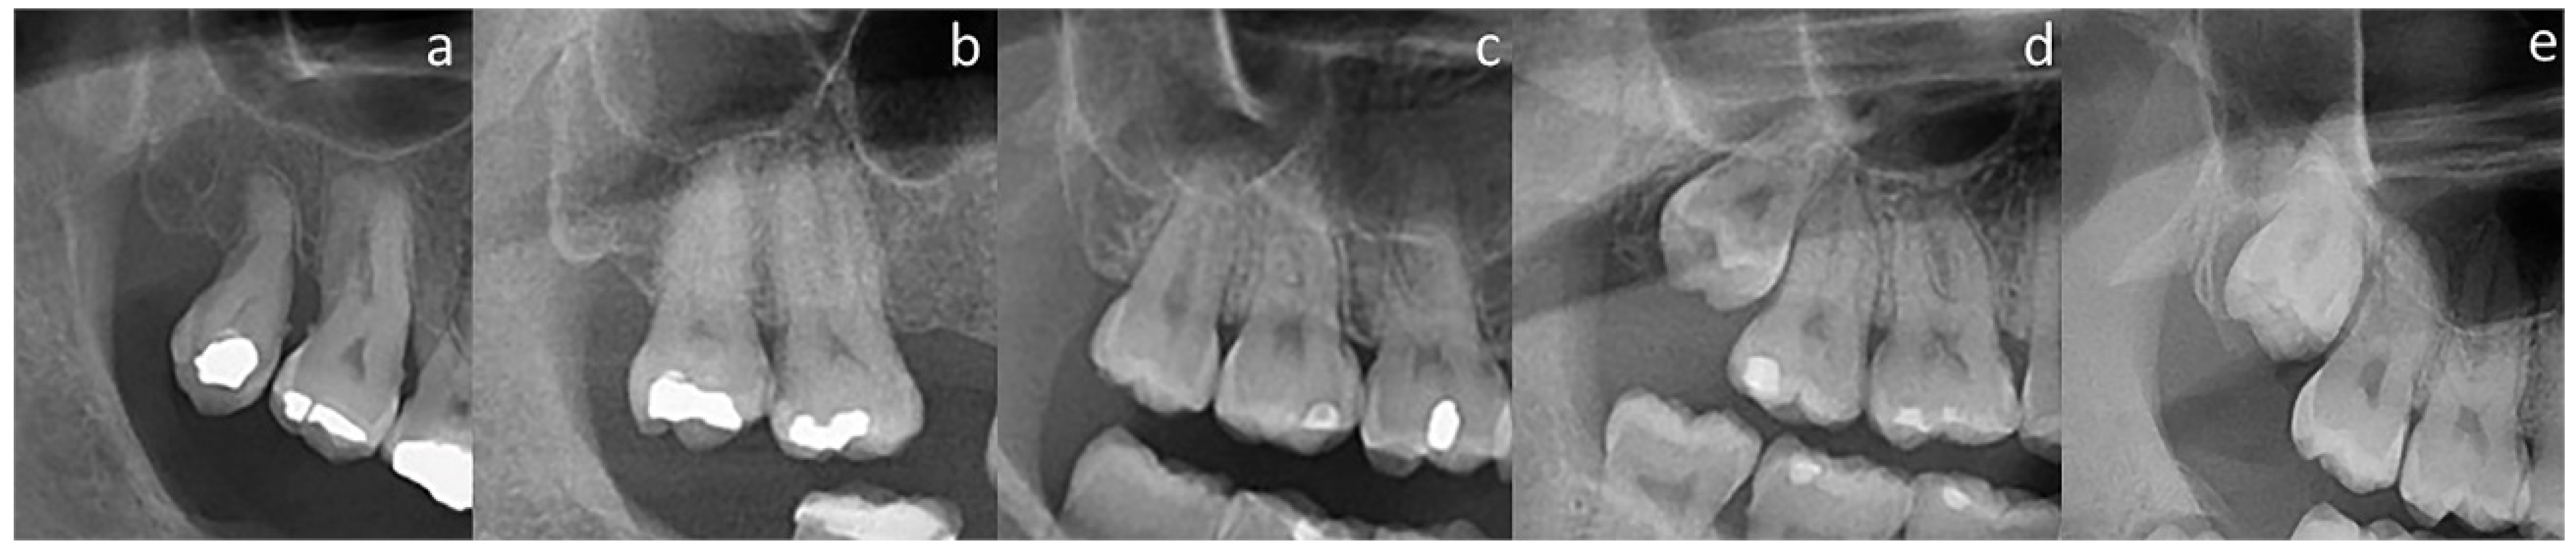

| Fused/Conical | Divergent | Dilacerated | Atypical | ||

| Fused/Conical | 130 (63.1%) | 20 (9.7%) | 11 (5.3%) | 5 (2.4%) | 166 (80.6%) |

| Divergent | 9 (4.4%) | 11 (5.3%) | 4 (1.9%) | 0 (0.0%) | 24 (11.6%) |

| Dilacerated | 4 (1.9%) | 0 (0.0%) | 10 (4.8%) | 0 (0.0%) | 14 (6.8%) |

| Atypical | 0 (0.0%) | 0 (0.0%) | 1 (0.5%) | 1 (0.5%) | 2 (1.0%) |

| Total | 143 (69.4%) | 31 (15%) | 26 (12.6%) | 6 (2.9%) | 206 (100%) |